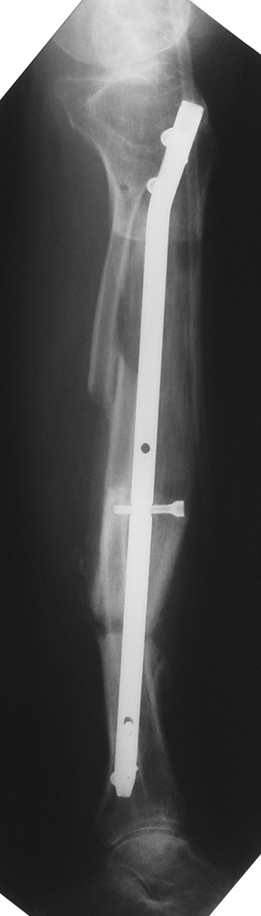

Uygun radikal debridman tüm nekrotik kemik ve yumuşak dokuların çıkartılmasını gerektirir, ve sıklıkla uzuvda instabiliteye neden olur. Kalan kemik ve yumuşak doku defektinin bir şekilde fiksasyonu ve rekonstrüksiyonu gereklidir. İlizarov’un ortaya koyduğu distraksiyon osteogenezi yöntemi, kaynamanın elde edilmesi, deformitenin düzeltilmesi, bacak boy eşitsizliğinin giderilmesi ve segmental defektlerin rekonstrükte edilmesi için başarıyla kullanılmaktadır.

Eksternal fiksatör ile geçen süre (eksternal fiksasyon indeksi), gereken distraksiyon miktarına bağlıdır ve bu süre boyunca bazı komplikasyonlarla karşılaşılabilir. Distraksiyon dönemi sona erdikten sonra, distraksiyon süresinin iki katını aşan konsolidasyon döneminde hastalar eksternal fiksatörü zorlukla tolere edebilirler. Yeterli konsolidasyon sağlanmadan eksternal fiksatör çıkartılırsa ise kırıklar, deformite ve kısalık oluşabilir. Hastanın fiksatör ile birlikte geçirdiği sürenin azaltılması ve böylece hasta konforunun ve aktivite düzeyinin arttırılması için intramedüller çivi üzerinden uzatma yöntemi uygulanmaktadır. Bu yöntemde distraksiyon dönemi sona erdiğinde kemiğin içindeki çivi statik olarak kilitlenmekte ve eksternal fiksatör çıkartılmaktadır. Stabilizasyon intramedüller çivi tarafından sağlandıktan sonra konsolidasyon dönemi gerçekleşmektedir. Bu şekilde hem eksternal fiksatörün uzun süre kalmasından hem de erken çıkartılmasından kaynaklanan komplikasyonların önüne geçilmektedir.